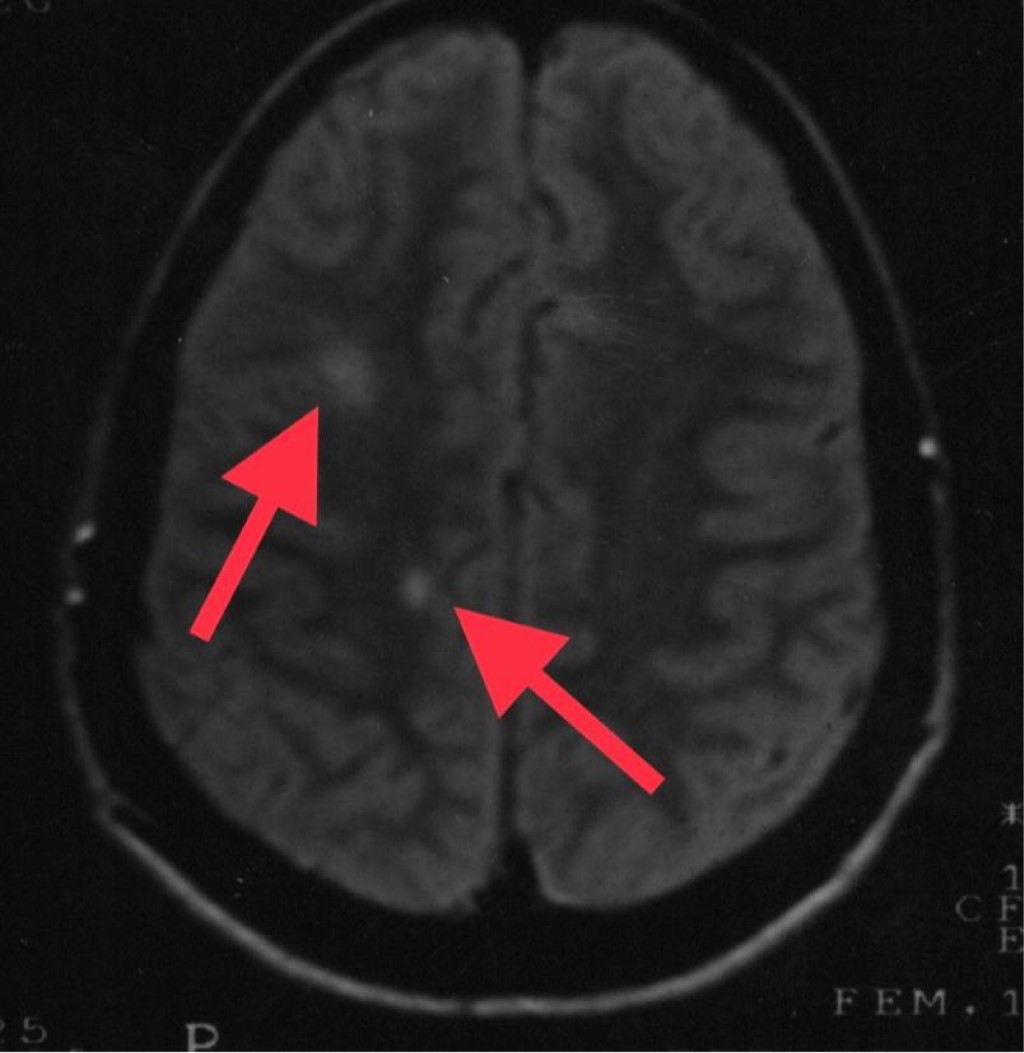

Objective: We describe two adolescent patients with multiple sclerosis, which is a demyelinating disease of the central nervous system. Presentation of the cases: The first case was a 14-year-old female patient with overweight; her condition was characterized by dizziness, headache, paresthesia in the lower limbs, diplopia and bradylalia. On physical examination, compatible data of cerebellar involvement were identified. A magnetic resonance imaging (MRI) of the skull showed areas of demyelination in the posterior fossa. Multiple sclerosis, the relapsing-remitting variety, is diagnosed. After the administration of steroids and beta interferon, there was improvement in symptoms. Second case: 13-year-old female, who presented fall from her own height, bladder incontinence, loss of strength in the left arm and leg. On physical examination, left hemiparesis was detected. MRI: demyelination data in lateral ventricle, cerebellum and spinal cord. The patient improved after starting steroids and interferon. Conclusions: The clinical presentation of multiple sclerosis in pediatric patients is a challenge, since it is a condition with unspecific manifestations. Establishing the diagnosis requires multiple studies. The earlier treatment is started, the more favorable the prognosis.

Figure 3